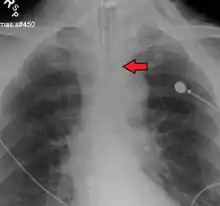

Ideally, at least one of the methods utilized for confirming tracheal tube placement will be a measuring instrument. Waveform capnography has emerged as the gold standard for the confirmation of tube placement within the trachea. Other methods relying on instruments include the use of a colorimetric end-tidal carbon dioxide detector, a self-inflating esophageal bulb, or an esophageal detection device.[35] The distal tip of a properly positioned tracheal tube will be located in the mid-trachea, roughly 2 cm (1 in) above the bifurcation of the carina; this can be confirmed by chest x-ray. If it is inserted too far into the trachea (beyond the carina), the tip of the tracheal tube is likely to be within the right main bronchus—a situation often referred to as a "right mainstem intubation". In this situation, the left lung may be unable to participate in ventilation, which can lead to decreased oxygen content due to ventilation/perfusion mismatch.[36]